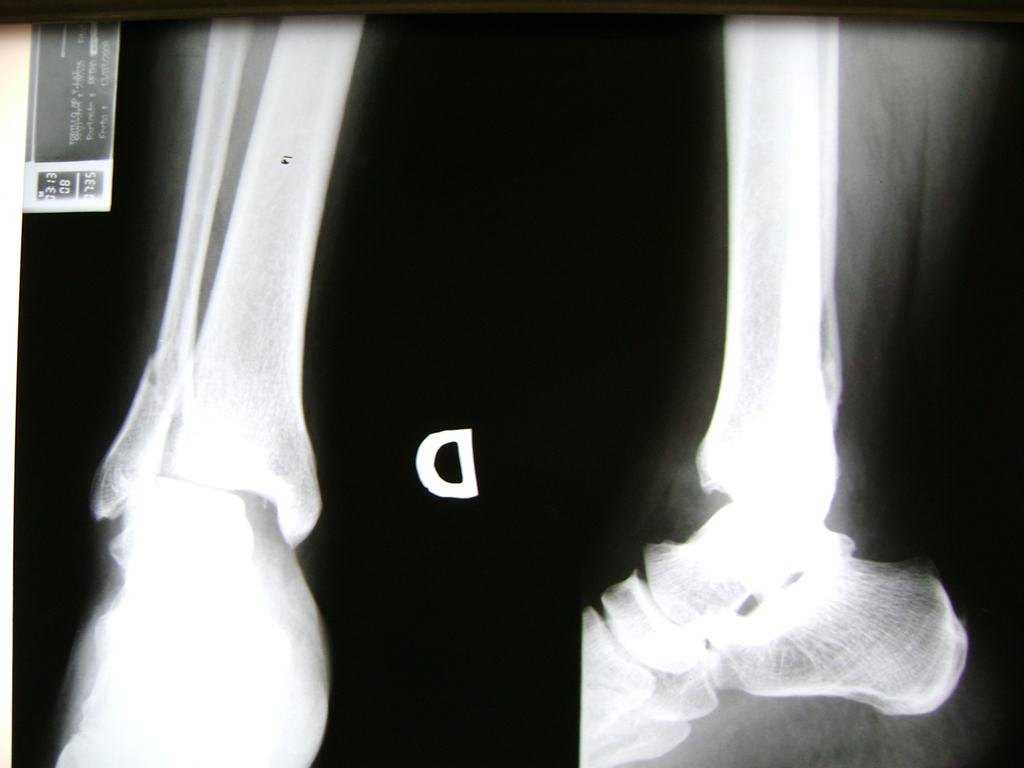

Cirugías de Peroné y Tibia

Una fractura de tobillo es la rotura de uno o más de los huesos del tobillo. Estas fracturas pueden ser:

Algunas fracturas de tobillo pueden requerir cirugía si:

Cuando se necesita cirugía, es probable que esta implique el uso de clavijas de metal, tornillos o placas para sostener los huesos en su lugar mientras la fractura se consolida. Los elementos de soporte pueden ser temporales o permanentes.